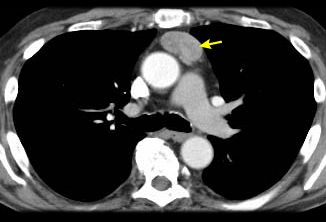

Tomografia computadorizada (TC) do tórax mostrando timoma com encarceramento e invasão da veia cava superior

Do acervo de Cameron Wright, MD; usado com permissão